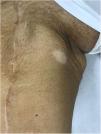

Piel. Formación continuada en dermatología Vitíligo asociado a tratamiento inmunomodulador del melanoma metastásico

Vitíligo asociado a tratamiento inmunomodulador del melanoma metastásico

Immunomodulatory therapy-associated vitiligo in metastatic melanoma